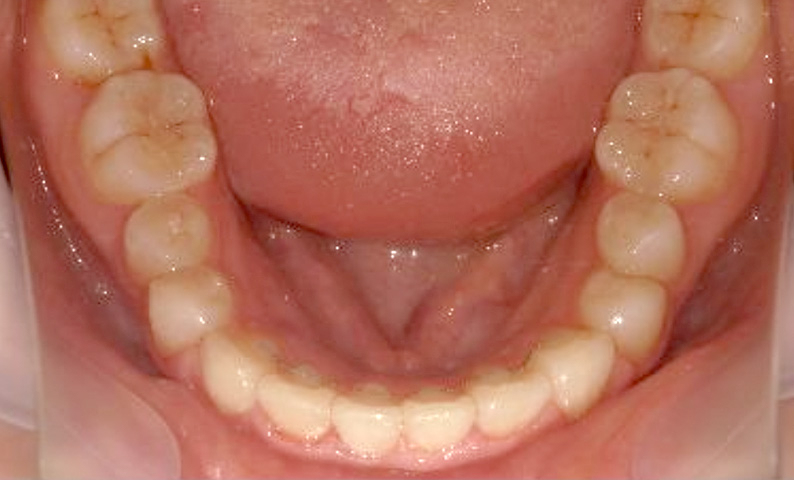

症例_025 上下顎の部分矯正

治療期間:13ヶ月金額:51万円+税女性前歯のガタガタ出っ歯